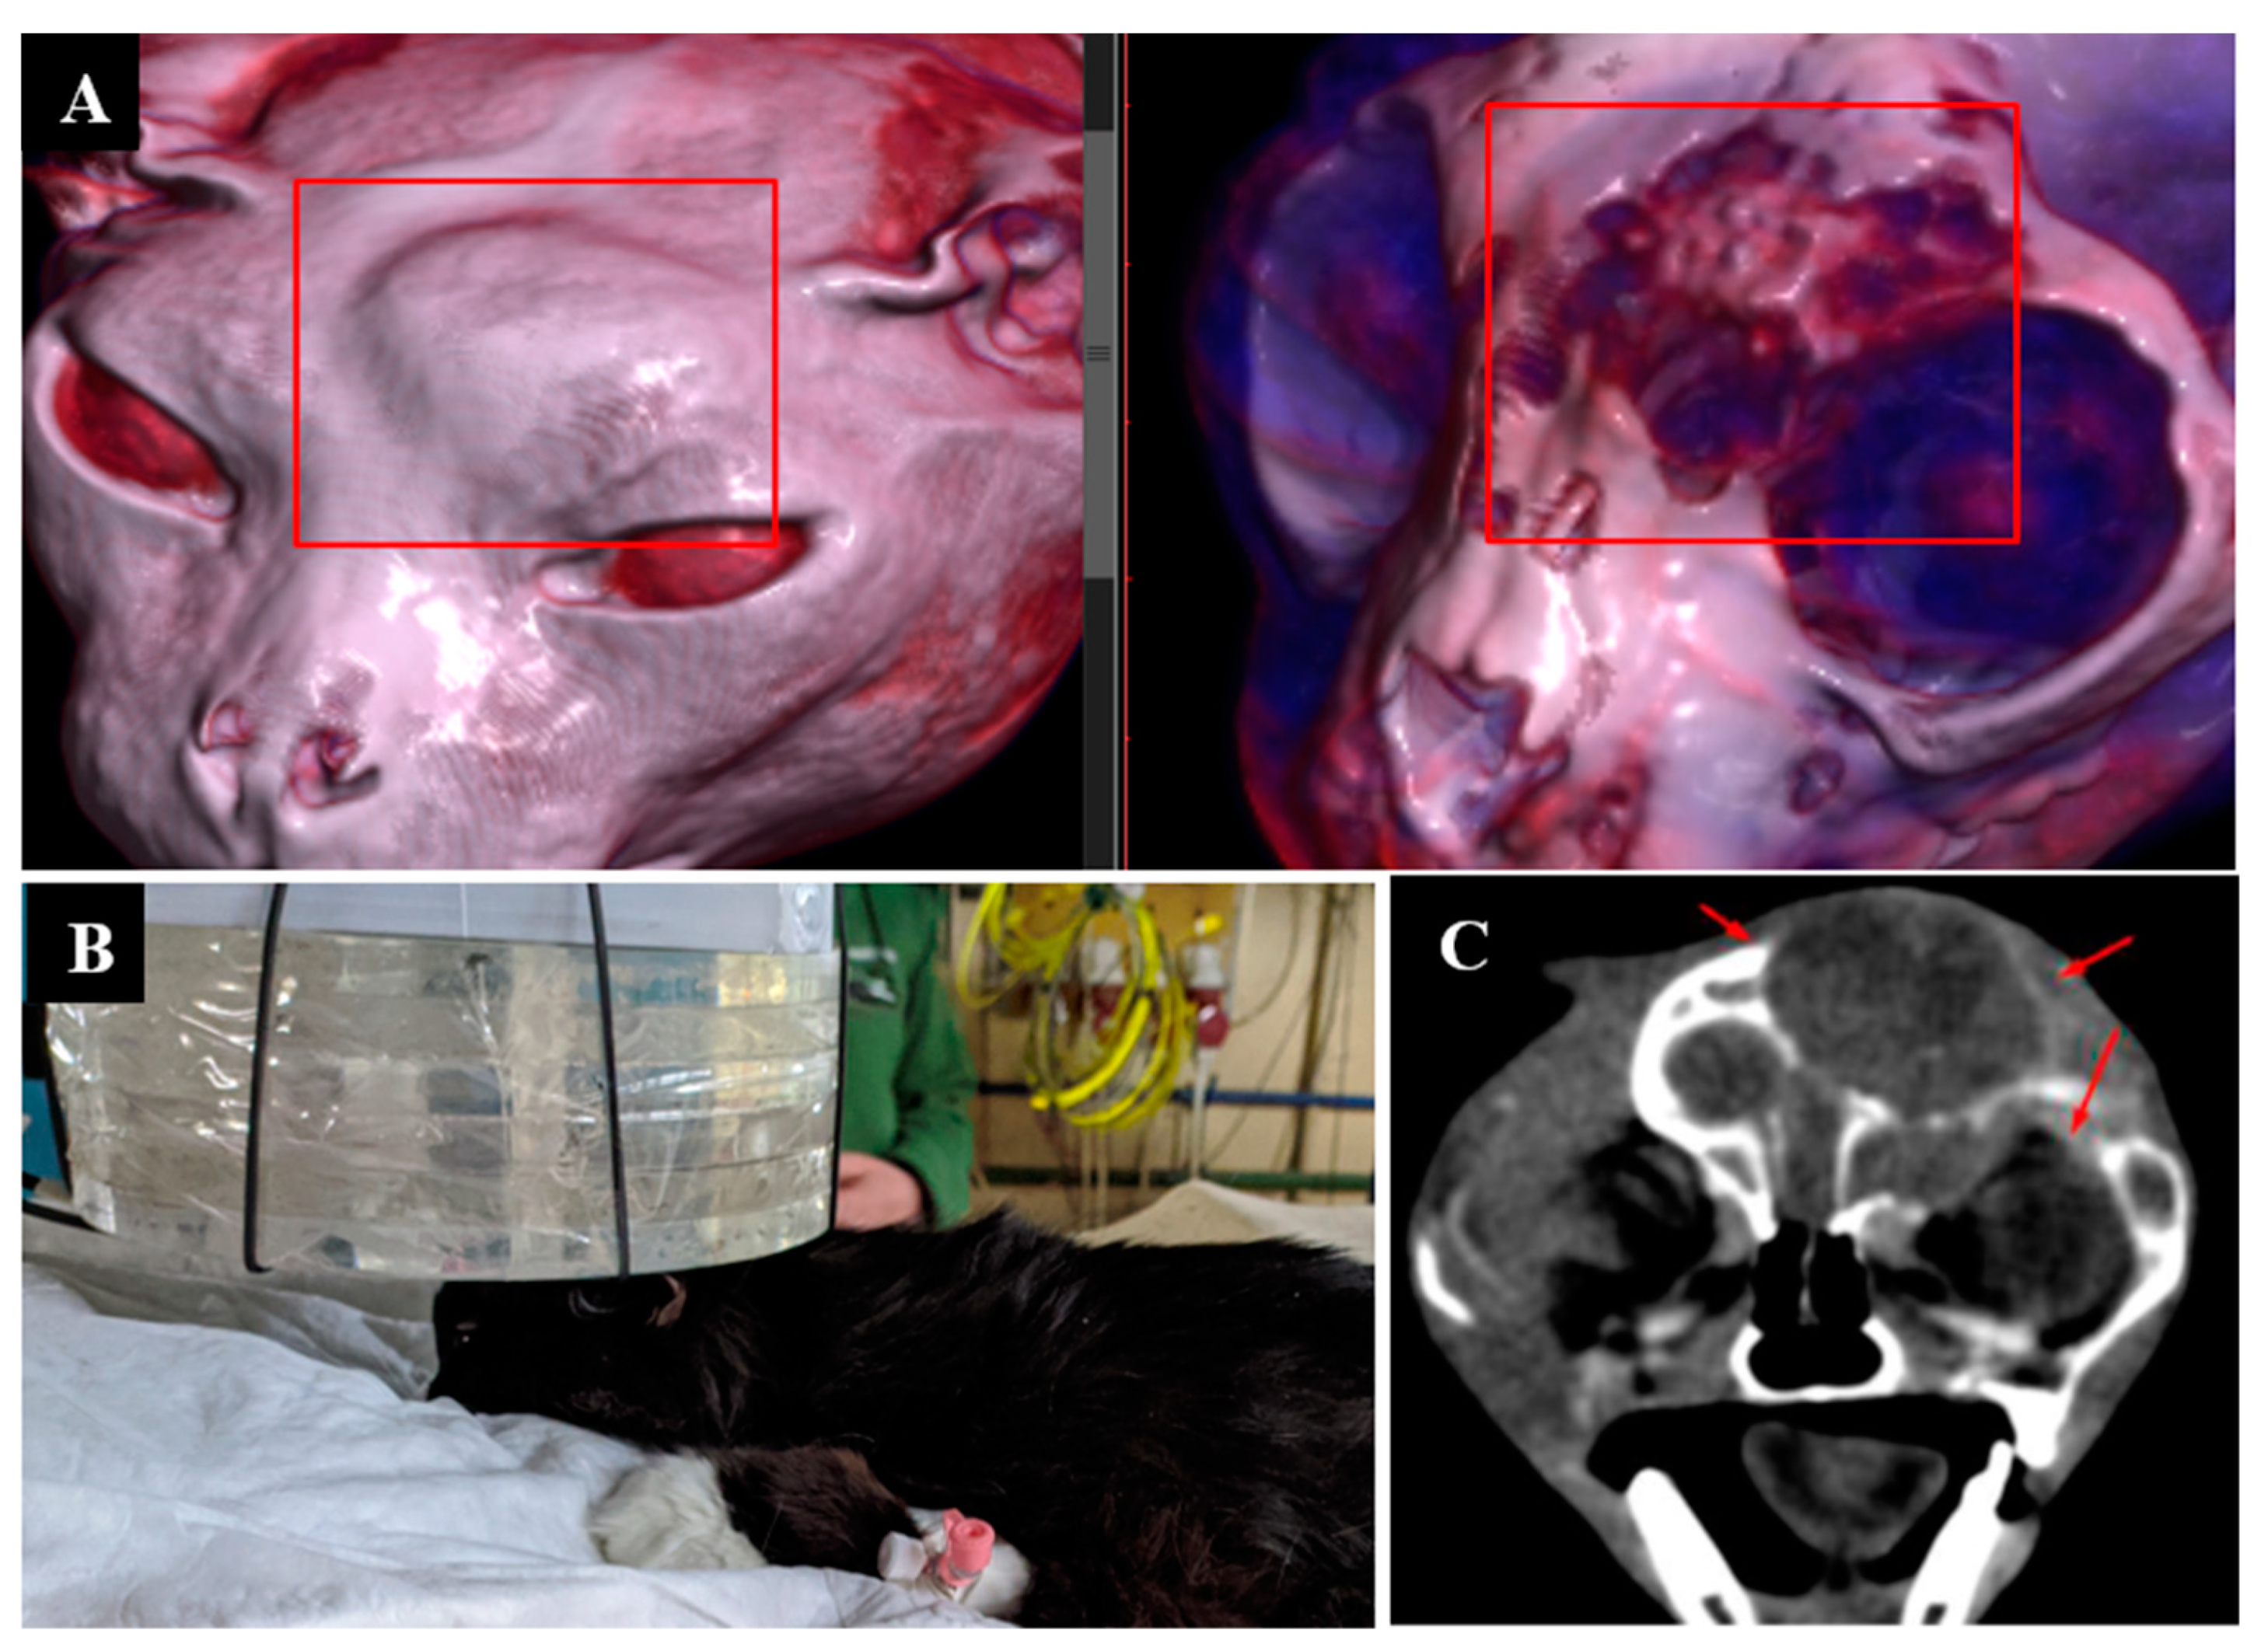

3.5. Case 5

3.6. Case 6

3.7. Case 7

3.8. Case 8